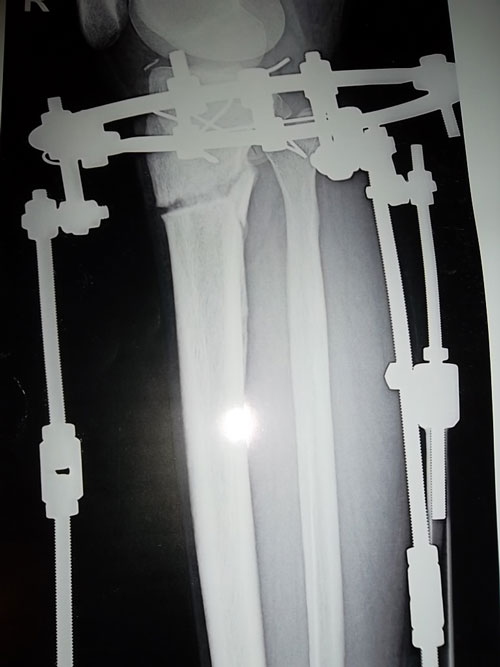

- Диагноз: О- образная деформация нижних конечностей

- Дата операции.: 30.01.2013

- Дата снятия аппаратов.: 04.05.2013

- Срок лечения.: 92 дня

На фиксации.Первый раз (на 23-ий день после операции) пошла без дополнительных средств опоры.

Первые самостоятельные шажки без дополнительных средств опоры на 23-ий день после операции.

Всем привет!Я с Алматы,мне 22.Приехала в Павлодар 24го сентября.25го утром сдала анализы,27го оперировали.После операций я не почувствовала боли и на следующий день я самостоятельно стала ходить с ходунком.Когда начила ходить были боли но терпимо.После операций на седьмой день вернее 4го ноября наш врач Н.Н начел крутить.Уже в тот день я увидела результат круток.Я в день ходила по 3,4часа.В общей сложности мне крутили ноги 15дней.А на последний день я увидела коласальный результат.На 23 день после операций начала ходить без ходунка.Спасибо нашему доктору.Руки у него золотые.Наконец-то мои мечты сбылись.И спасибо девченкам которые меня поддерживали.